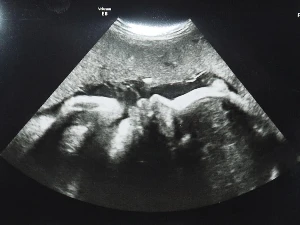

A szülésznő szokásosan nagyon kedves volt, pontosan kitapogatta a Babácskát, és megerősítette, hogy még lejjebb van a kis feje, mint két hete. Sőt, már valóban a célegyenesben, biztosan szépen dolgozik már a méhszájon, idő kérdése, hogy meginduljon. Aztán eljött a kiírt nap, és még semmi. Itt amúgy ezzel nem nyomasztják az anyukákat, két hét múlvára kaptam egy következő időpontot. Ha addig se történik semmi, akkor felajánlják a burok méhszájról való leválasztását (membrane sweep; ezt a szülésznő két ujjal csinálja, és a folyamat proglandin hormont szabadít fel, ami a méhszáj felpuhulásáért felelős, ezért 24-48 órán belül általában beindul a szülés). De ez még nagyon messze van! Addigra csak megunja a helyhiányt bent ez a kicsi Lány!